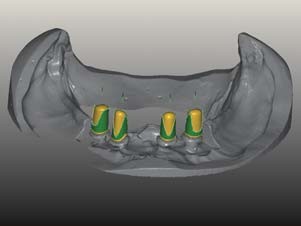

Nach viermonatiger Einheilzeit wurden die Implantate bei reizlosen Weichgewebsverhältnissen freigelegt, Ober- wie Unterkiefer geschlossen und indexiert abgeformt und die Situation mit Zahnfleischmaske auf das Meistermodell übertragen (Abb. 11–14). Die Wahl des geeigneten Abutments richtete sich nach der Dicke der periimplantären Mukosa, wie sie in der Zahnfleischmaske widergespiegelt ist, und der Position der Implantate im Verhältnis zu der ästhetischen Position aus der Wachsaufstellung. Klebebasen waren aufgrund der dünnen periimplantär-mukosalen Verhältnisse ungeeignet. Einteilige Abutments aus Zirkonoxid schieden wegen des Belastungsaspektes im Seitenzahnbereich aus. Die Ästhetik von titannitridbeschichteten Titanabutments kommt bei Teleskopprothesen nicht zur Geltung. Daher waren individuelle Titanabutments die erste Wahl. Nach einer Ästhetikeinprobe wurden die individuellen Abutments auf Basis der gescannten Ober- und Unterkiefermodelle bei ATLANTIS gestaltet und angefertigt. Zur Beschleunigung des Produktionsprozesses wurden die Modelle mithilfe des für ANKYLOS passenden ATLANTIS FLO (Feature Locating Object, DENTSPLYImplants, Mannheim) im Labor gescannt (3Shape D700, Kopenhagen) und die Daten digital übermittelt.

Um die Retentionsflächen zu vergrößern, wurden sie anschließend im Labor mit 120μm Aluminumoxid abgestrahlt (Abb. 15–19). Die individuellen Abutments wurden eingescannt und darauf die Primärteile aus in A3 eingefärbtem Zirkonoxid angefertigt. Design und Herstellung der Zirkonprimärteile erfolgten direkt im Labor (Modellier- Software und Fräseinheit Zirkonzahn, Gais) In der Software wurde die Innenpassung der Primärkronen optimal den jeweiligen Abutments angepasst. Die Parallelität der Teleskope zueinander bzw. die Gesamteinschubrichtung wurden ebenfalls am Bildschirm festgelegt. Die auf einen Konuswinkel von 2 Grad gefrästen Primärteile wurden unter Wasserkühlung im Parallelfräsgerät feingeschliffen und anschließend mit Diamantpolierpaste auf Hochglanz poliert. Eine „spiegelglatte“ Oberflächenqualität der Zirkonoxid-Primärkrone und ein nur minimaler Spalt zwischen Patrize und Matrize von ca. 5 μm sind entscheidend für eine perfekte Funktion. Eine Präzision, die ohne Scannertechnologie und CAD/CAM-Fertigung nicht erzielbar wäre.